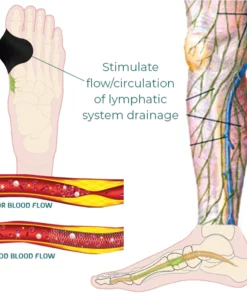

- This patch aids in stimulating the lymphatic system, which helps lymph fluids move throughout the body and improve circulation, as well as reducing pain and swelling, accelerating metabolism, and easing stiff joints.